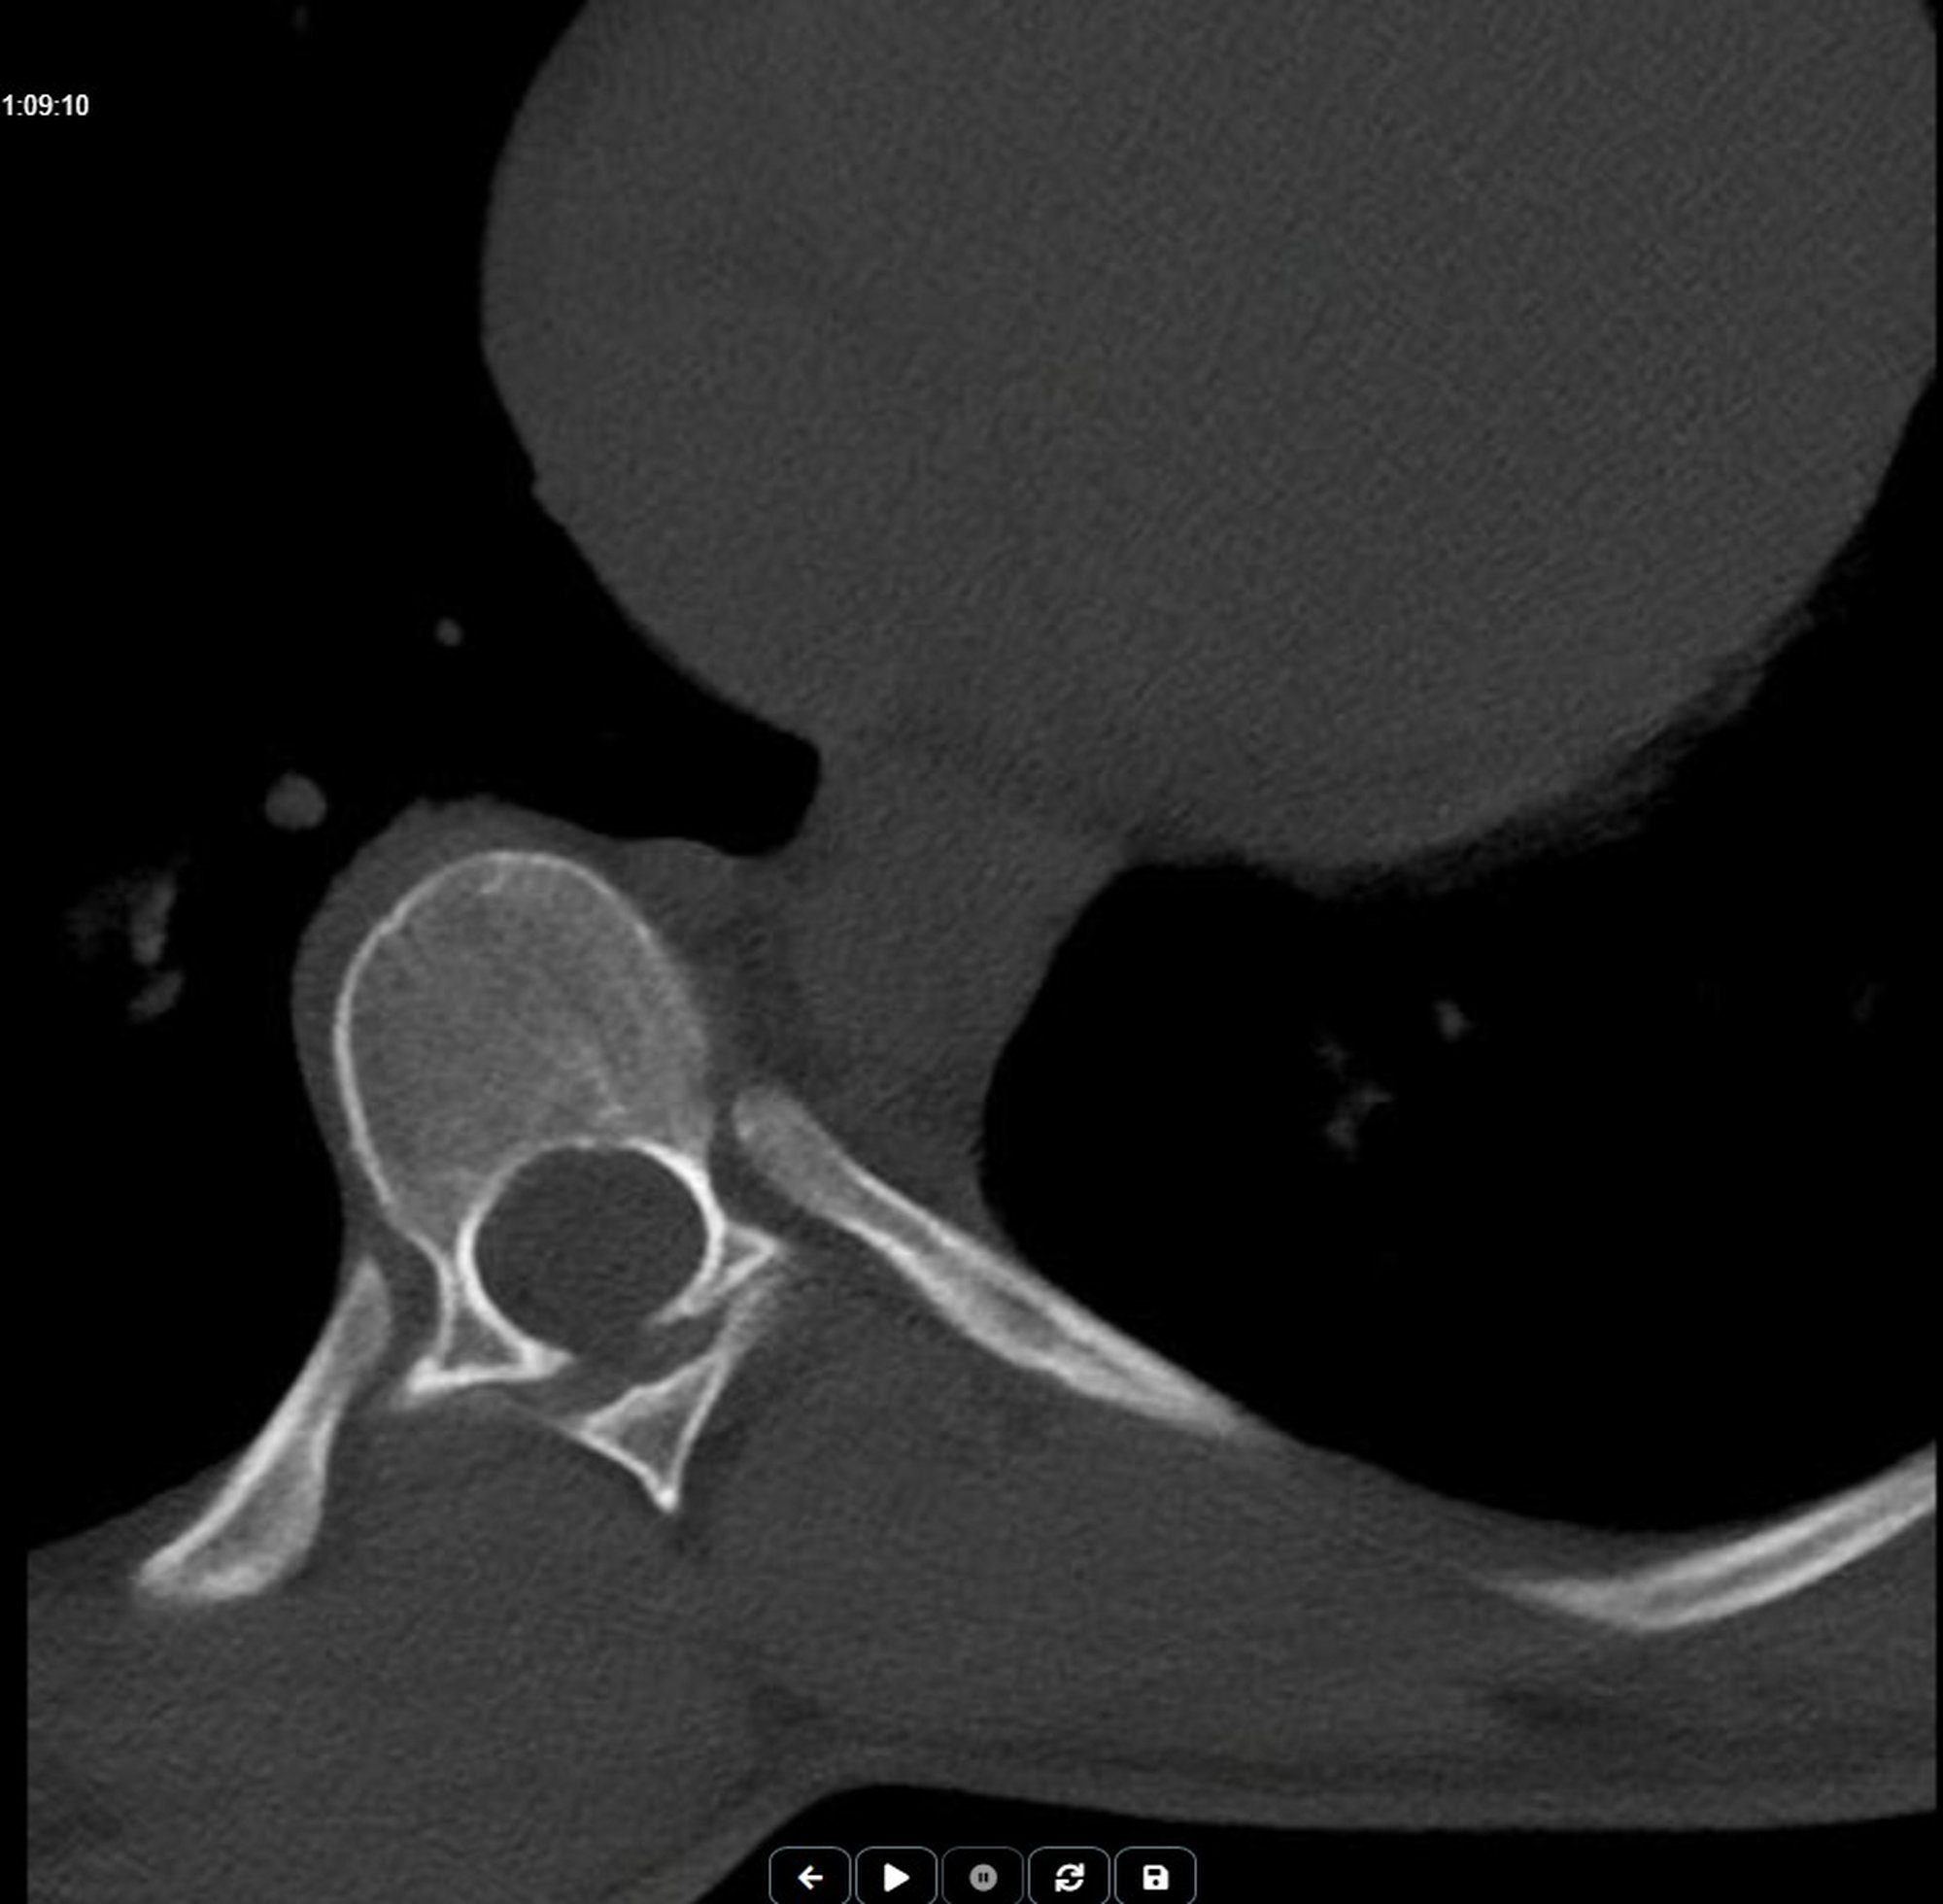

Skolyozun nereden başlayıp nerede bittiğini, ne yöne doğru olduğunu incelemek için MR görüntülerime bakıyordum. Eğriliğin belirgin olarak başladığı kısımda kalp de başlıyor. kalbin çapının en büyük olduğu kısım eğriliğin en fazla olduğu kısım ve bittiği yerdeyse diyafram başlıyordu. Ben de yüz üstü yatmaktan kalbin omurları itebileceğini düşündüm.